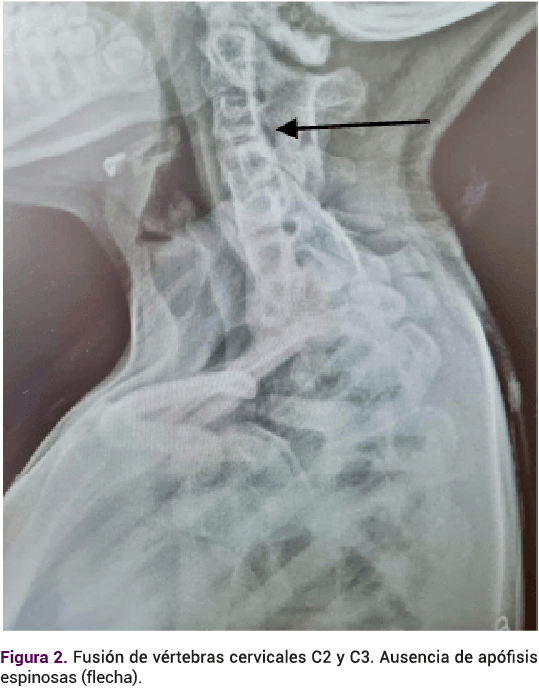

Adolescente de 14 años, que acudió a consulta debido a la amenorrea primaria. Antecedentes relevantes: embarazo conseguido mediante técnicas de fertilización in vitro. Durante la etapa prenatal se le diagnosticó riñón en herradura. En los primeros días de nacida el ultrasonido reportó: ectasia pielocalicial y requirió cateterismo. En la exploración neonatal se apreciaron fisuras palpebrales antimongoloides, paladar ojival, epicanto interno, puente nasal amplio y genitales externos femeninos. El cariotipo 46XX, sin alteraciones estructurales. La valoración audiológica fue normal. A los 8 y 10 años requirió cateterismo ureteral por síntomas urológicos. La radiografía de columna cervicotorácica por escoliosis, tomada a los 12 años, reportó una fusión costal posterior derecha del primero al cuarto arco, hemivértebras C6, C7 y T1, además de fusión de los cuerpos vertebrales de C2 y C3. Ausencia de apófisis espinosas de C5 hasta C7. Figuras 1 y 2

Alteraciones esqueléticas. La afección más común es la escoliosis en la columna cervical (17%), pero suelen ser diversas, como agenesia de toda la vértebra, hemivértebras segmentadas, fusión vertebral o vértebra en bloque (anomalía de Klippel-Feil) 4%.4,23,24